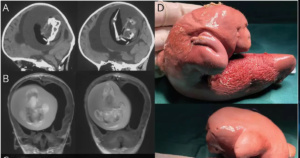

Σύμφωνα με τις φωτογραφίες, η εμβρυϊκή μάζα είχε αναπτύξει άνω άκρα και προεξοχές που έμοιαζαν με δάκτυλα.

Οι γιατροί στο Πανεπιστήμιο Fudan στη Σαγκάη εξήγησαν ότι το παιδί παρουσίασε διευρυμένο κεφάλι και προβλήματα με τις κινητικές της δεξιότητες. Οι αξονικές τομογραφίες του κεφαλιού της έδειξαν ότι ο εγκέφαλός της ήταν συμπιεσμένος και ότι υπήρχε συσσώρευση υγρού που προκλήθηκε από μια σημαντικού μεγέθους μάζα.

Οι λεπτομέρειες στην σχετική δημοσίευση δεν είναι κατατοπιστικές, αλλά οι συγγραφείς περιγράφουν ότι πραγματοποιήθηκε χειρουργική αφαίρεση, που αποκάλυψε μια σπάνια περίπτωση “ενδοκοιλιακού εμβρύου μέσα σε έμβρυο”!